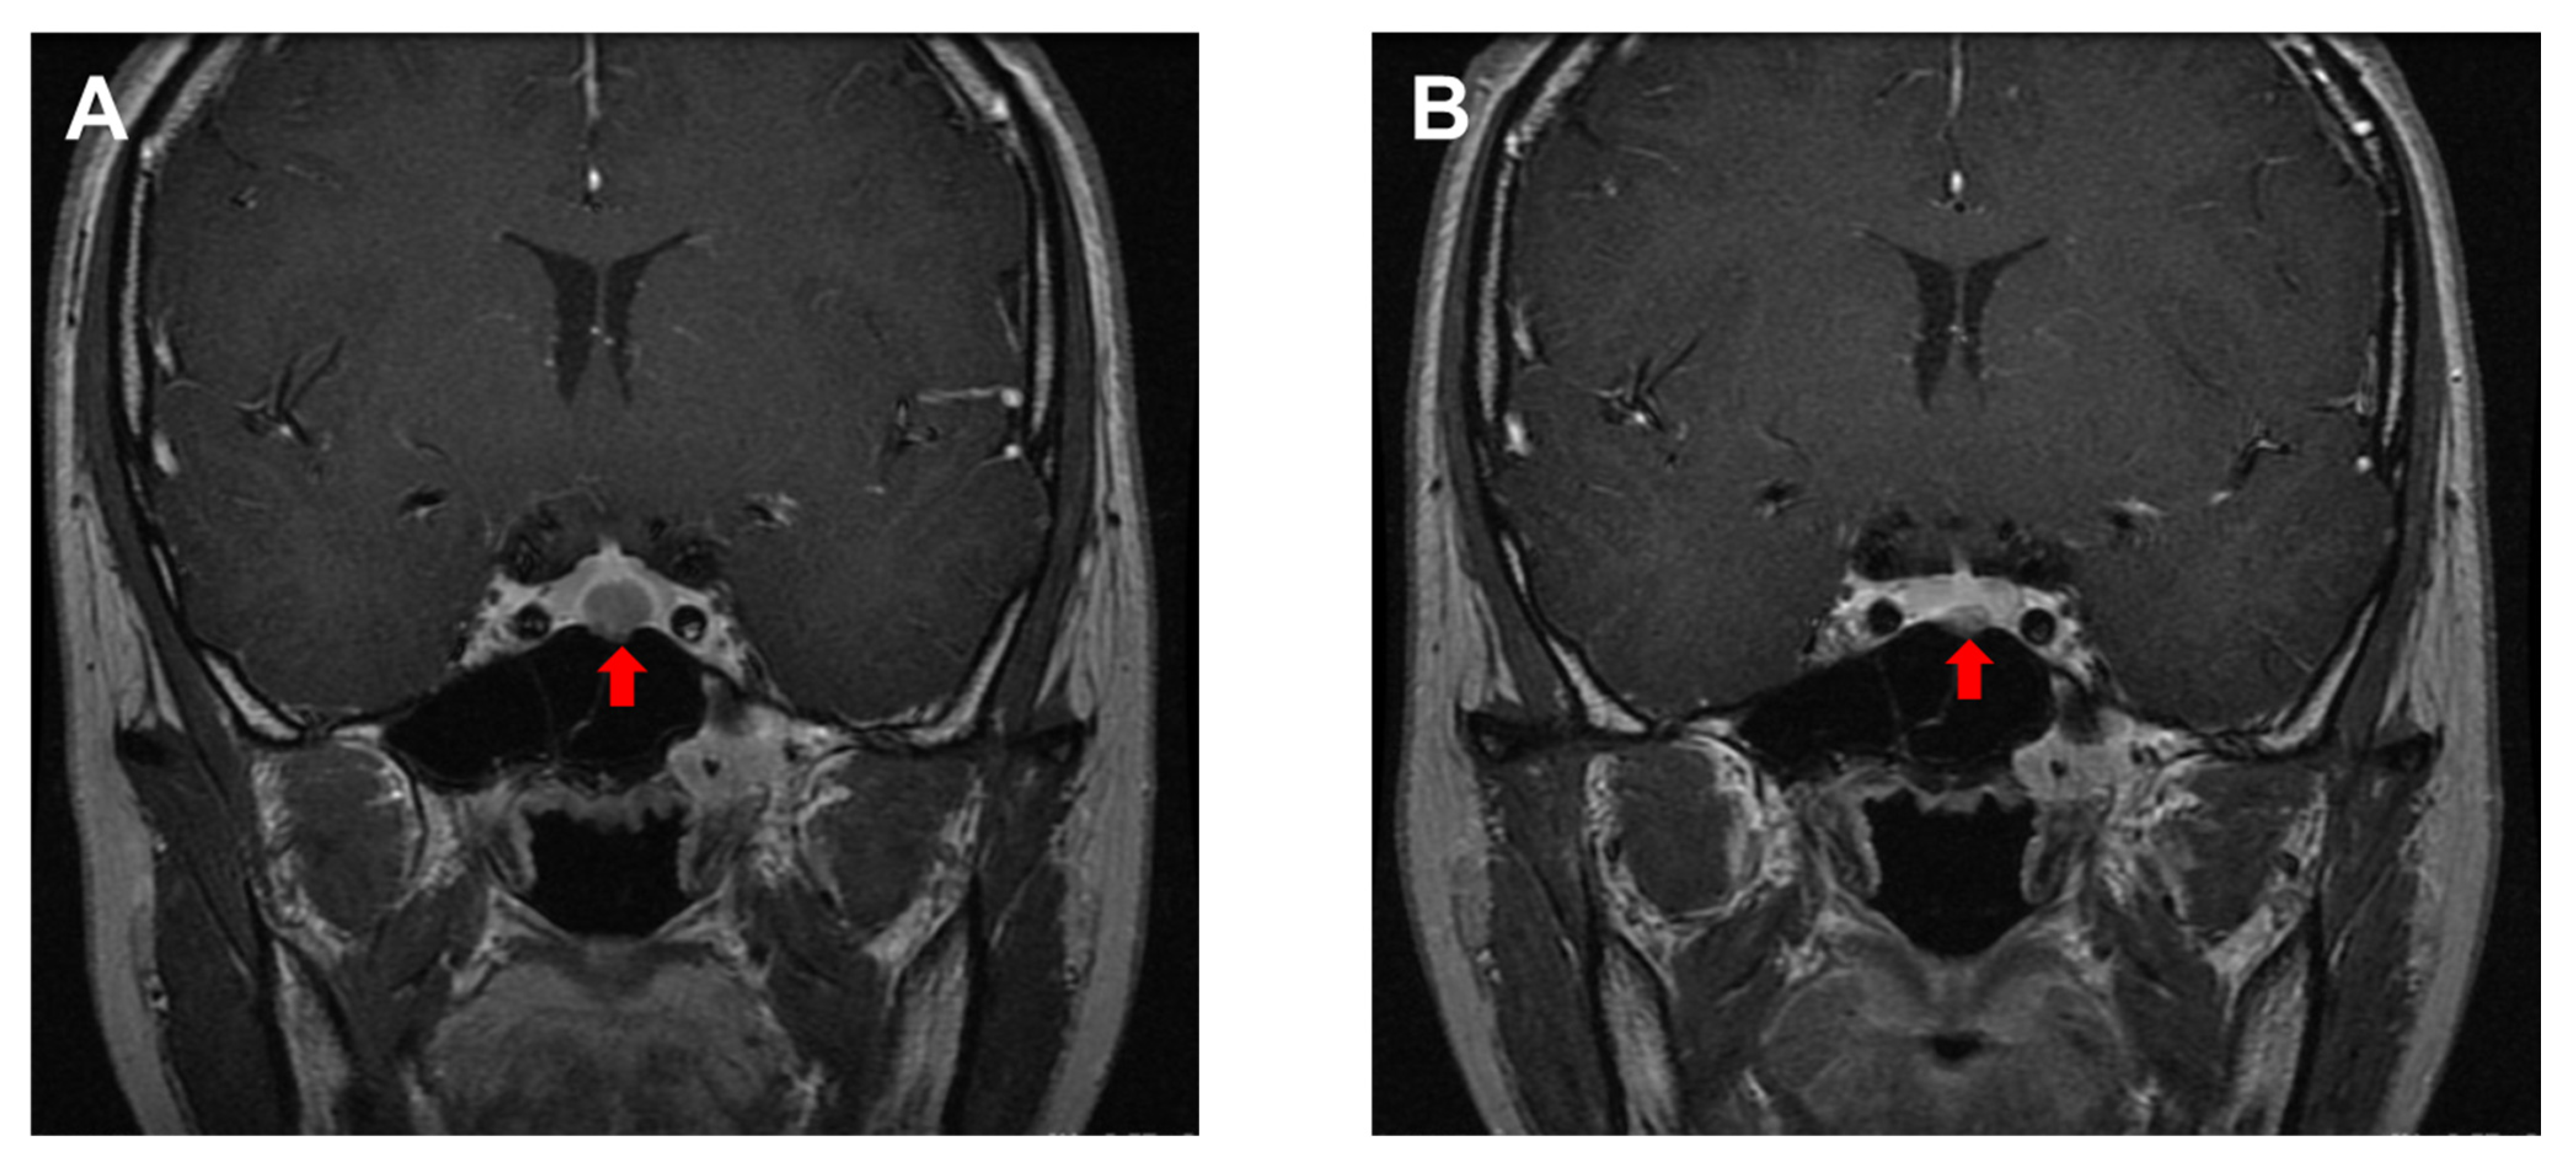

- Burlacu, M.C.; Maiter, D.; Duprez, T.; Delgrange, E. T2-weighted magnetic resonance imaging characterization of prolactinomas and association with their response to dopamine agonists. Endocrine 2019, 63, 323–331. [Google Scholar] [CrossRef]